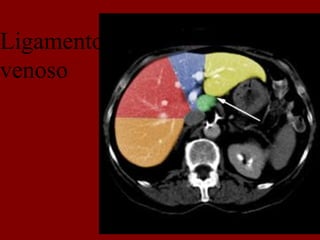

INCISÃO SOBRA A VEIA HEPÁTICA DIREITA

INCISÃO SOBRE A VEIA HEPÁTICA MÉDIA.

INCISÃO SOBRE A VEIA HEPÁTICA ESQUERDA.

Cissura transversa(horizontal)

Cissura vertical

Ligamento

venoso

INCISÃO SOBRA AVEIA HEPÁTICA DIREITA

INCISÃO SOBRE AVEIA HEPÁTICA MÉDIA.

INCISÃO SOBRE AVEIA HEPÁTICA ESQUERDA.